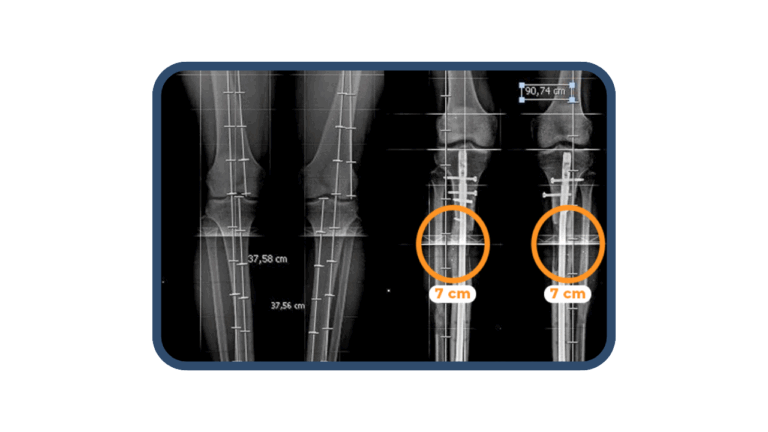

En las consultas especializadas en alargamiento óseo, el Dr. Christian Huamaní explica detalladamente el proceso de elongación de fémures y tibias. La consulta es complementada con la telerradiografía realizada a los pacientes, la cual es fundamental para conocer y explicar a los pacientes acerca de la cantidad (centímetros) que pueden elongar sus articulaciones.

En la cirugía de alargamiento óseo se realiza el método LON, el cual permite reducir el tiempo de permanencia del fijador externo (HMC). El procedimiento consiste en realizar una fractura controlada en el hueso (fémur o tibia). Luego, se coloca un clavo endomedular dentro del hueso , junto al fijador externo HMC que es unido a la extremidad, gracias a agujas percutáneas llamados Schantz. Nuestra cirugía de alargamiento óseo, suele durar 2 horas aproximadamente. La hospitalización alrededor de 5 días, para seguidamente continuar con el plan de recuperación preparado por Arthrosalud.